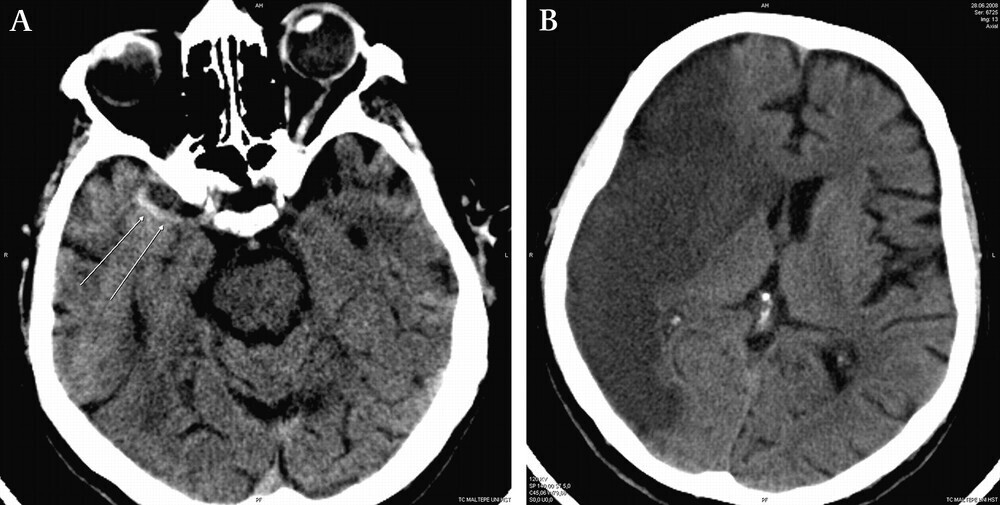

다음으로 알아볼 질환은 뇌경색입니다. "경색"이라는 단어는 우리가 흔히 듣는 "경제가 경색되었다"라는 표현과 비슷한데요. 뇌경색은 뇌 혈관이 막혀서 혈액이 흐르지 않는 상태를 말합니다. 이 때문에 뇌 조직이 손상을 입고 마비 증상이 나타날 수 있습니다.

이렇게 말하면 뇌출혈과 뇌경색이 뇌졸중이라는 것을 알 수 있습니다. 그런데 사실 뇌출혈은 뇌경색이 진행된 후에 발생하는 경우가 많습니다. 하지만 뇌경색을 인지하지 못한 상태에서 갑작스럽게 혈관이 파열되어 뇌출혈이 발생할 수도 있으며, 고혈압과 같은 기저 질환을 가진 사람들이나 온도 변화가 급격한 겨울철에 혈압이 높아져 혈관이 터지기도 합니다.

요약하자면, 뇌졸중은 뇌 혈관의 문제로 인해 발생하는 질환을 의미합니다. 뇌출혈은 뇌 혈관이 터져서 출혈이 생기는 것이며, 뇌경색은 뇌 혈관이 막혀서 혈액 공급이 끊기는 것입니다. 이렇게 뇌졸중은 두 가지 형태로 구분할 수 있습니다.